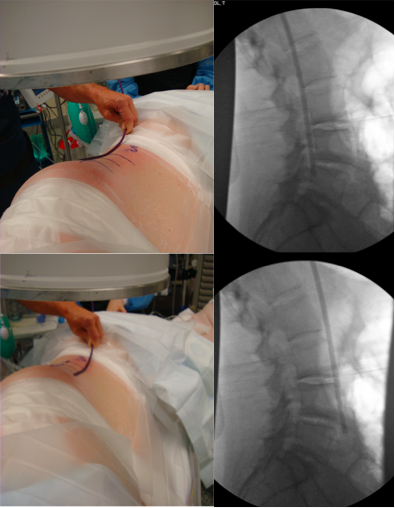

16. Karikari IO, Nimjee SM, Hardin CA, Hughes BD, Hodges TR, Mehta AI, et al. Extreme lateral interbody fusion approach for isolated thoracic and thoracolumbar spine diseases: initial clinical experience and early outcomes. J Spinal Disord Tech 2011;24(6):368-75. doi: 10.1097/BSD.0b013e3181ffefd2

29. Taher F, Hughes AP, Sama AA, Zeldin R, Schneider R, Holodny EI, et al. 2013 Young Investigator Award winner: How safe is lateral lumbar interbody fusion for the surgeon? A prospective in vivo radiation exposure study. Spine (Phila Pa 1976). 2013;38(16):1386-92. doi: 10.1097/BRS.0b013e31828705ad